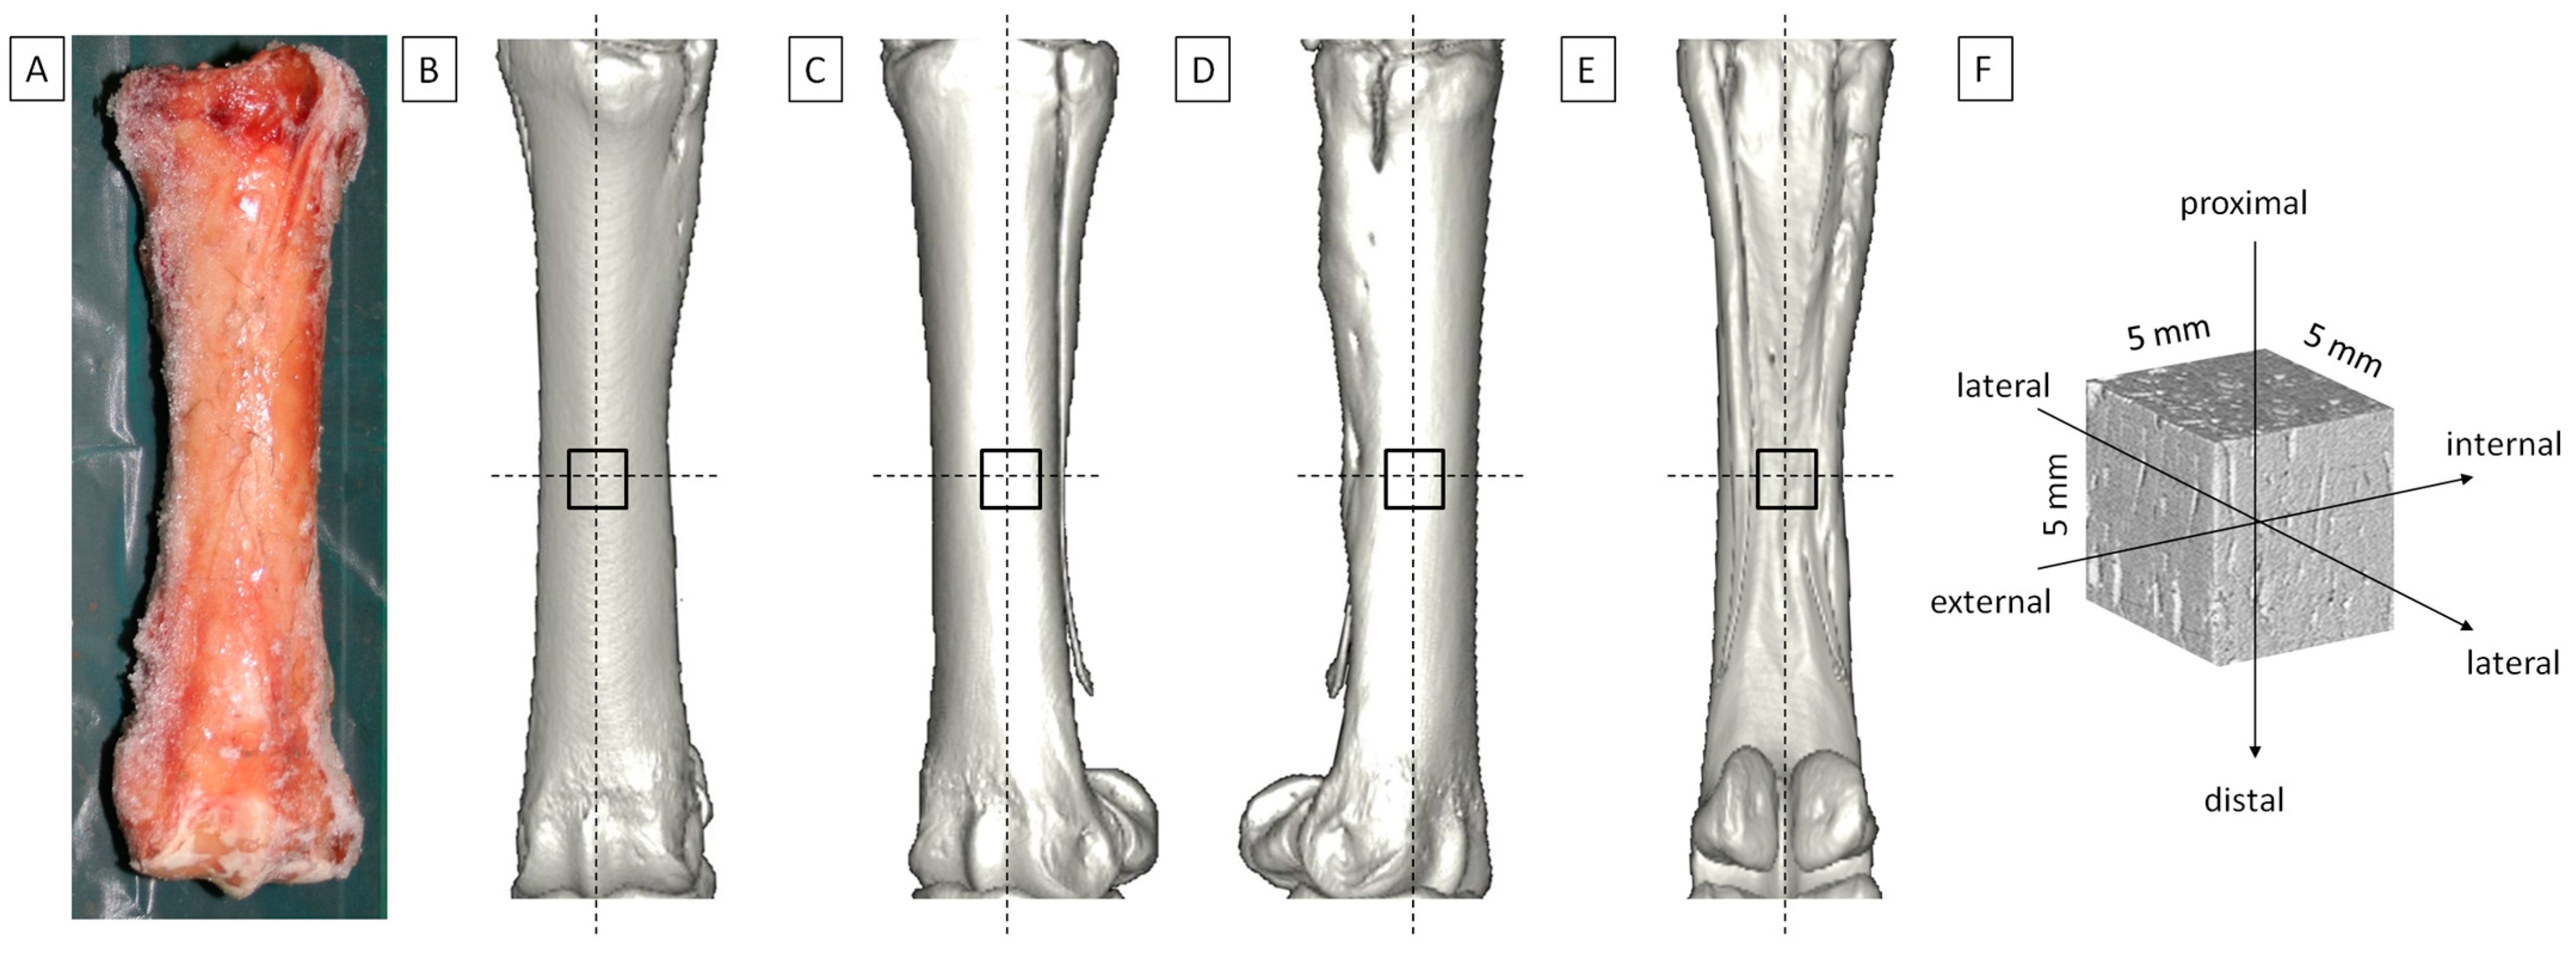

2.1. Biological Samples

2.2. CT Imaging